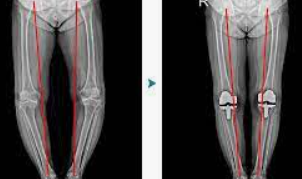

인공 관절 수술은 관절의 퇴행성 변화, 외상, 또는 다른 질환으로 인해 손상된 관절을 인공적인 재료로 만든 관절로 교체하는 의료 절차입니다. 이 수술은 주로 무릎, 고관절, 어깨 관절 등에 적용되며, 환자의 삶의 질을 향상시키고 통증을 감소시키는 데 목적이 있습니다.

인공 관절 수술의 종류는 크게 두 가지로 나뉩니다: 전치환술과 부분치환술입니다. 전치환술은 손상된 관절 전체를 인공 관절로 교체하는 방법이며, 부분치환술은 손상된 관절의 일부만을 교체하는 방법입니다. 환자의 상태와 필요에 따라 적절한 수술 방법이 선택됩니다.

전치환술은 관절의 변형이 심하거나 손상 부위가 넓은 경우에 주로 사용됩니다. 이 수술은 관절의 안쪽과 바깥쪽 모두를 인공 관절로 바꿔줌으로써, 통증을 줄이고 관절의 기능을 회복시키는 데 도움을 줍니다.

최근에는 로봇 인공관절 수술이 도입되어, 수술 과정에서 발생할 수 있는 정상 조직의 손상과 출혈을 최소화하고, 수술 부위를 신속하고 정확하게 절개할 수 있어 회복이 빠르고 재활이 용이해졌습니다.